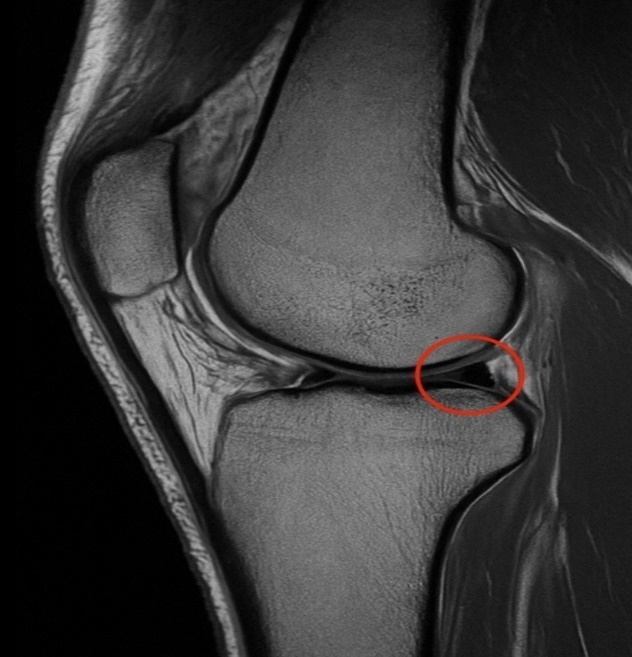

Empiric broad-spectrum intravenous antibiotics were initiated with meropenem and vancomycin, and two sets of blood cultures were drawn. Imaging with MRI of the knee ruled out joint effusion or deep abscess formation (Figure 1).

T2-weighted sagittal MRI of the right knee revealing a horizontal tear in the posterior horn of the medial meniscus